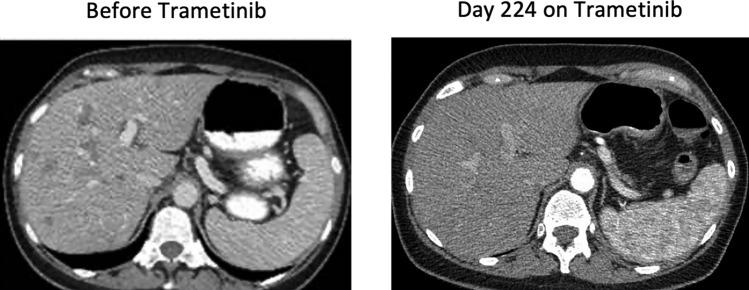

Published preclinical and clinical data have demonstrated limiting results in the response of non-V600 mutated cancers to targeted therapies. Response rates were variable for the major classes of BRAF mutations including class II and class III mutations as well as, BRAF fusions. Data collected from our INOVA cohort offered promising results with one patient achieving partial remission and two patients achieving stable disease.

已发表的临床前和临床数据表明,非 V600 突变型癌症对靶向治疗的反应有限。主要 BRAF 突变类别(包括 II 类和 III 类突变以及 BRAF 融合)的反应率各不相同。从我们的 INOVA 队列收集的数据提供了有希望的结果,一名患者实现部分缓解,两名患者实现稳定疾病。